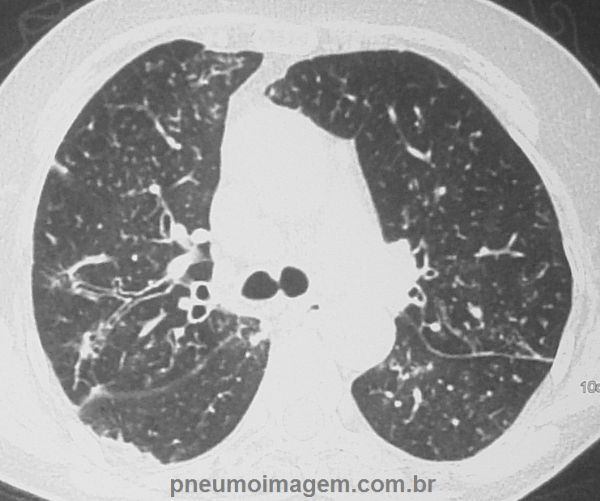

Opacidades em vidro fosco nos lobos superiores, de predomínio subpleural, associadas a área de bronquiectasias.

Neste corte ainda observa-se nos lobos superiores a presença de nódulos centrolobulares e áreas de impactação mucóide.